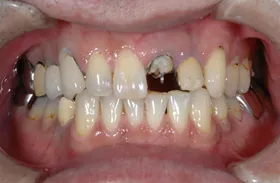

■治療前

■治療後

| 主訴 | しっかりかみたい(咬合障害) |

| 治療方法 | 費用を抑える為、全てインプラントではなく、インプラントを土台とした入れ歯の治療 |

| 治療期間 | 約6か月 |

| 通院回数等 | 約20回 |

| 費用 | 約150万円 |

| リスク・副作用 | 術後の腫れ・痛み |